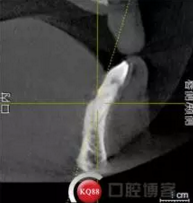

檢查:上頜無(wú)牙頜假牙穩(wěn)定性尚可,下頜3435364243殘根;33殘冠1-2度松動(dòng),其他牙齒缺失;CBCT檢查:下頜牙槽骨前牙區(qū)骨高度足,后牙區(qū)骨高度最低為8mm,骨寬度足。

1)術(shù)前檢查,拍攝臨床照片及CBCT檢查,制取活動(dòng)義齒參考模型,指導(dǎo)后期最終修復(fù)的牙齒排列

2)術(shù)前準(zhǔn)備及手術(shù)過(guò)程,測(cè)量血壓及血糖,簽種植知情同意書;嚴(yán)格遵循無(wú)菌操作,局麻下采用微創(chuàng)技術(shù)于323436分別植入osstem4.0X10,4.0X10,4.5X7; 434446分別植入osstem4.0X1O,4.0X10,4.5X7.初期穩(wěn)定性均達(dá)到了35N.CM以上;嚴(yán)密縫合,止血,種植體位點(diǎn)和方向與設(shè)計(jì)一致。